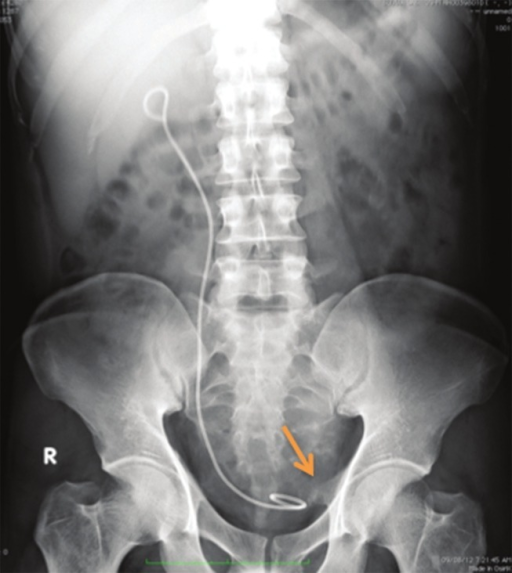

Case number: 2. X-ray of urinary bladder, taken on 03 O | Open-i

Minimally invasive percutaneous cystostomy with ureteroscopic pneumatic …

The kidney, ureter and bladder (KUB) X-ray shows a retained stent with …